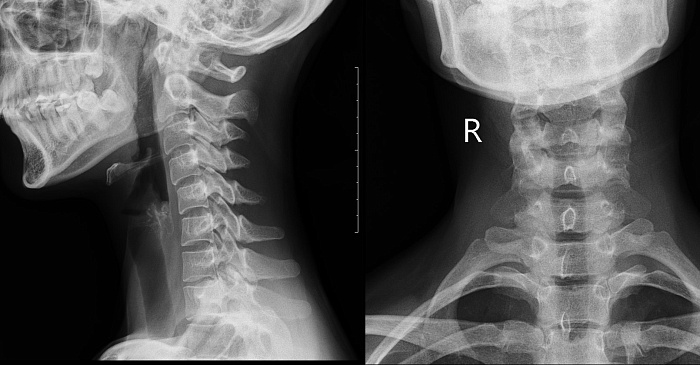

2. Рентгенография сочленения затылочной кости и первого шейного позвонка

Прицельное исследование сочленения затылочной кости и первого шейного позвонка, выполняется в прямой проекции.

Показания для проведения исследования:

• головные боли;

• боли и дискомфорт в шее при повороте головы;

• слабость в одной или обеих руках;

• вывих/подвывих первого шейного позвонка;

• артроз атланто-дентального сочленения.